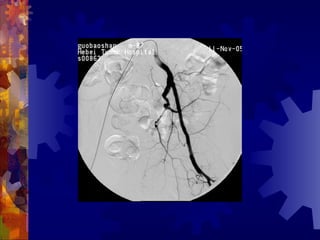

糖尿病足的检查

4. 足部 X- 线检查

5. 动脉造影(下肢)

6. 溃疡表面分泌物的培养

男, 86 岁

双下肢多普勒血流图未探及血管

动脉造影血管闭塞